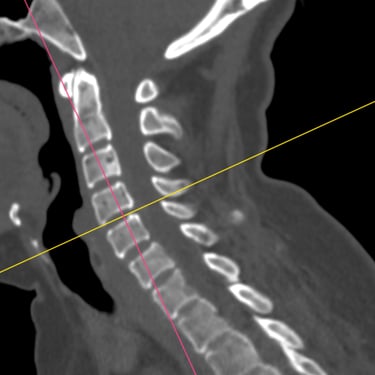

La hernia cervical es una causa frecuente de dolor en el cuello, hormigueo en los brazos y debilidad muscular. Cuando el tratamiento conservador no alivia los síntomas, la cirugía de discectomía cervical con artrodesis (ACDF) se convierte en una excelente alternativa. Este procedimiento consiste en retirar el disco dañado que comprime los nervios y reemplazarlo con un injerto o prótesis que estabiliza la columna. La ACDF ofrece alta tasa de éxito, mejorando el dolor, la fuerza y la calidad de vida. Gracias a técnicas modernas y una recuperación controlada, muchos pacientes vuelven rápidamente a sus actividades habituales.